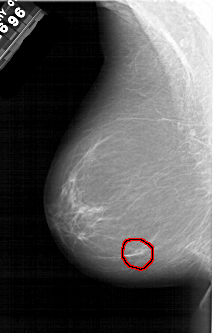

A_1308_1.RIGHT_MLO

RIGHT_CC LINES 5986 PIXELS_PER_LINE 3391 BITS_PER_PIXEL 12 RESOLUTION 43.5 NON_OVERLAY

RIGHT_MLO LINES 6511 PIXELS_PER_LINE 4246 BITS_PER_PIXEL 12 RESOLUTION 43.5 NON_OVERLAY